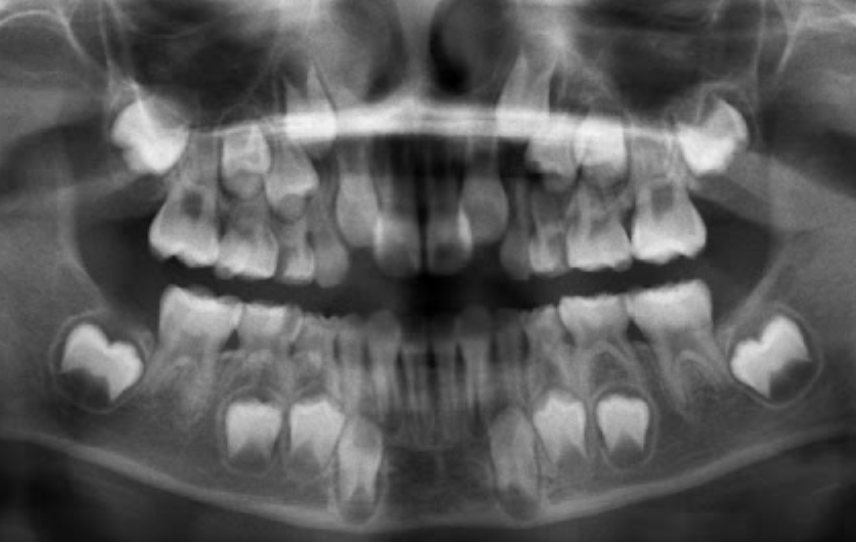

1.Ad. LOWER central incisors present? Yes. definitely 6-7 or older

1. Ad. UPPER CI present? Yes def. 7-8 y.o

3.Ad. Upper LAT incisor present (baby sheds 7-8)? NO so still under 7-8

Conc: pt is under 7